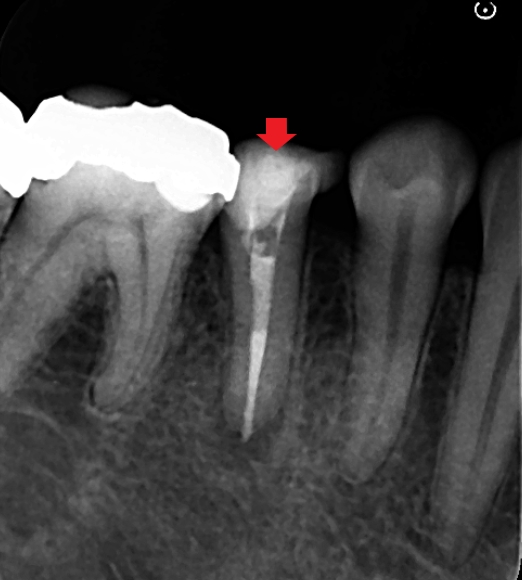

精密根管治療を行い、根の先までしっかり根管充填をすることを心がけました。画像は根管充填時のレントゲン写真です。根の先まで根管充填材が届いています。